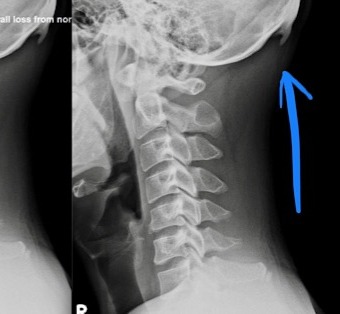

The X-ray with the blue arrow is of a 29 year old male with a horn growing out of the back of his head that has recently been diagnosed or classified by a group of Australian Chiropractors as an Occipital Spur. Their experience with these Occipital Spurs were recently covered by the Washington Post.

Whatever it is, it is obviously not normal. When the body senses injury on or near bone, it recruits calcium. That's how your body heals a broken bone, by recruiting calcium. As a result of the constant stress of looking down into a phone, the body senses injury to the attachment point on the occiput for all of the extensors muscles of the head, so it recruits calcium, which then accumulates to form this ugly and symptomatic spur. This patient (only 29 years old) has severe neck pain and headaches. We have 10 docs in our chiropractic clinics here in Singapore and each of us have at least 2-3 patients with Occipital Spurs.